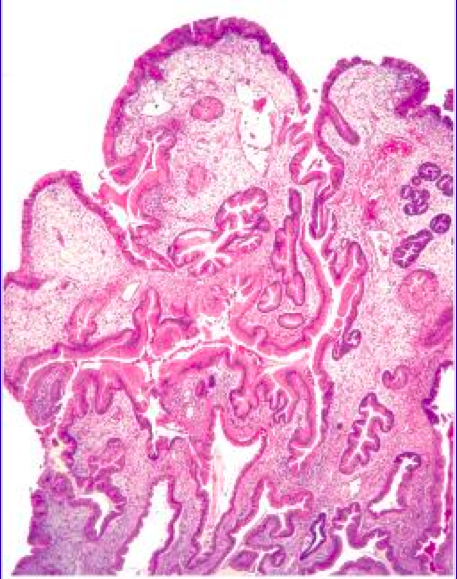

<p>What kind of stomach polyp?</p>

<p>Peutz-Jegers (hamartomatous) Polyp</p>

<ul>

<li>arborizing smooth muscle layer</li>